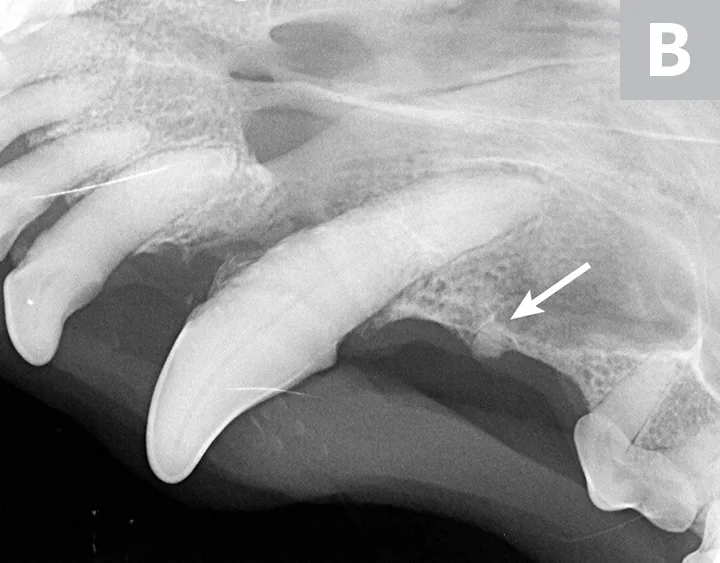

Figure 2

Dental radiographs of the right (A) and left (B) maxillary canine teeth (lateral views) and the rostral maxillae (C; occlusal view) confirmed mild horizontal and severe vertical bone loss at the mesial aspect of both maxillary canine teeth. Moderate to severe horizontal bone loss at the right maxillary first incisor tooth (blue arrow) and total loss of attachment with inflammatory root resorption at the right maxillary second incisor tooth (yellow arrow) were present. The remaining maxillary incisor teeth were affected by mild horizontal bone loss. Although the occlusal view of the rostral maxillae is slightly asymmetric, osteolysis was evident in the area of the left palatine fissure (red arrow). Mild horizontal bone loss was diagnosed at several other teeth. In addition, retained root tip of the left maxillary (presumably) first premolar tooth (white arrow) was identified.